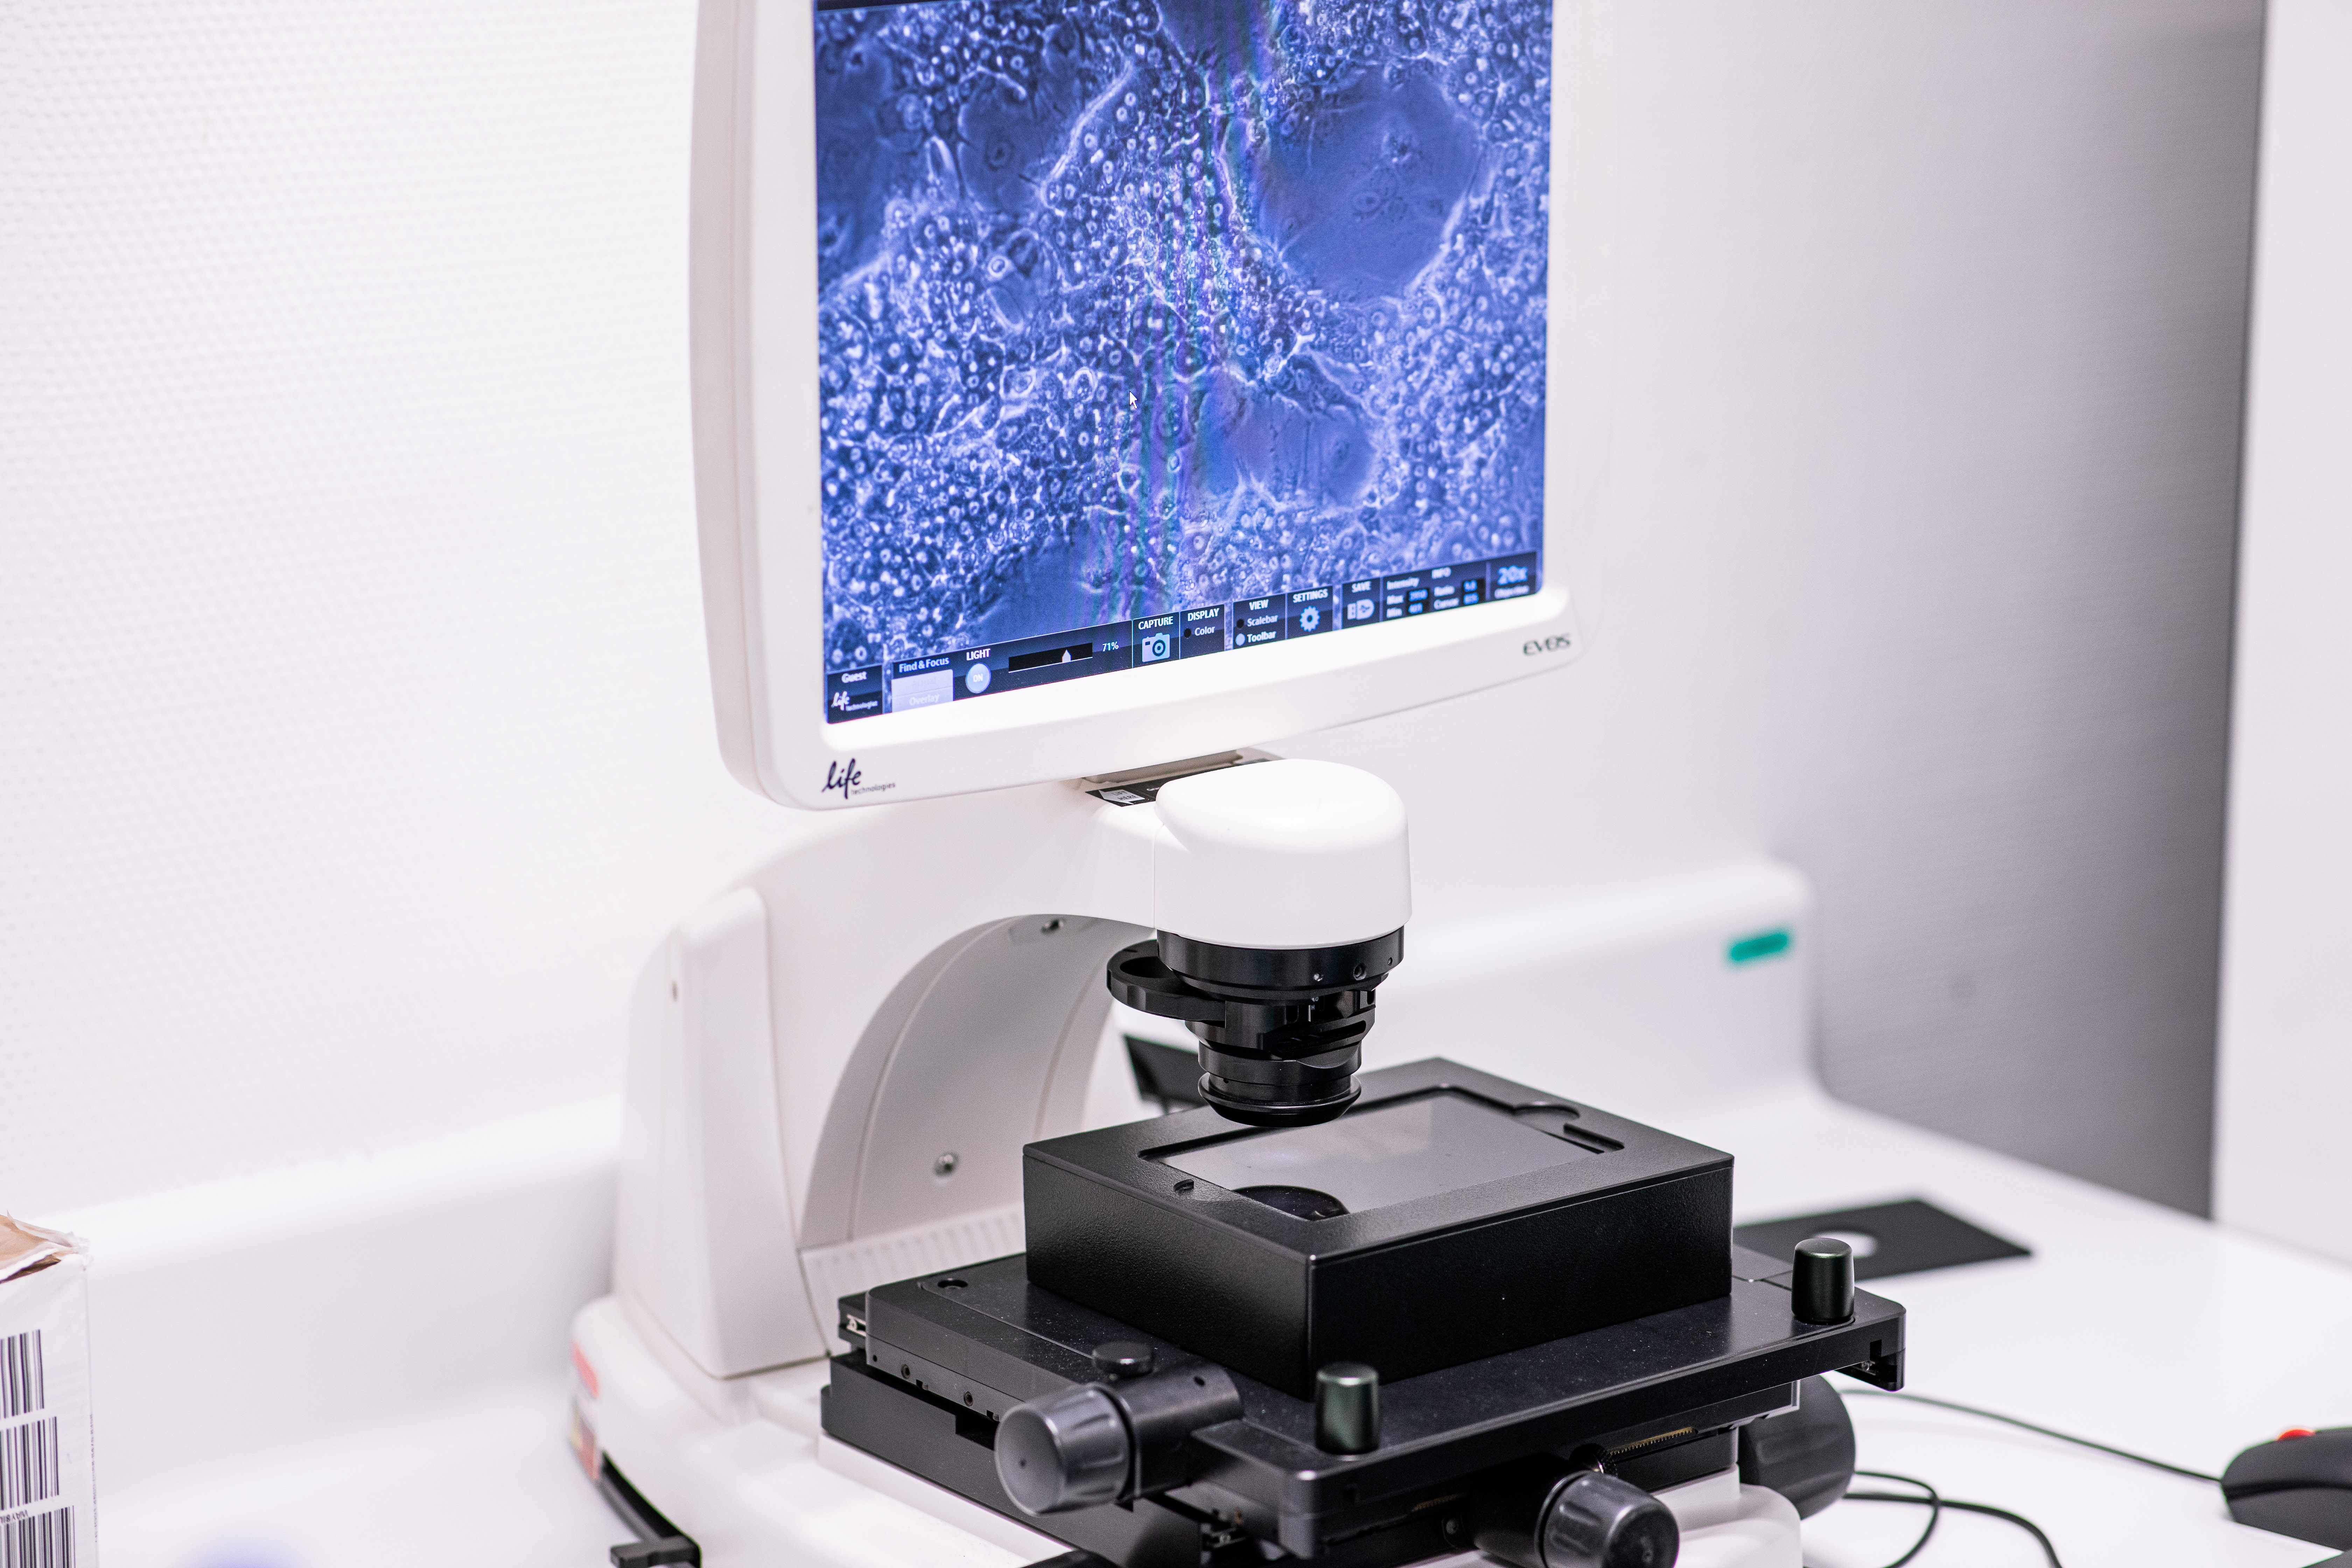

We are a biotech group that provides solutions for assessing fate and safety of drugs, cosmetics and industrial compounds.

Our expertise in biological and chemical systems

We innovate at the forefront of biotechnology and safety assesment since 90's.